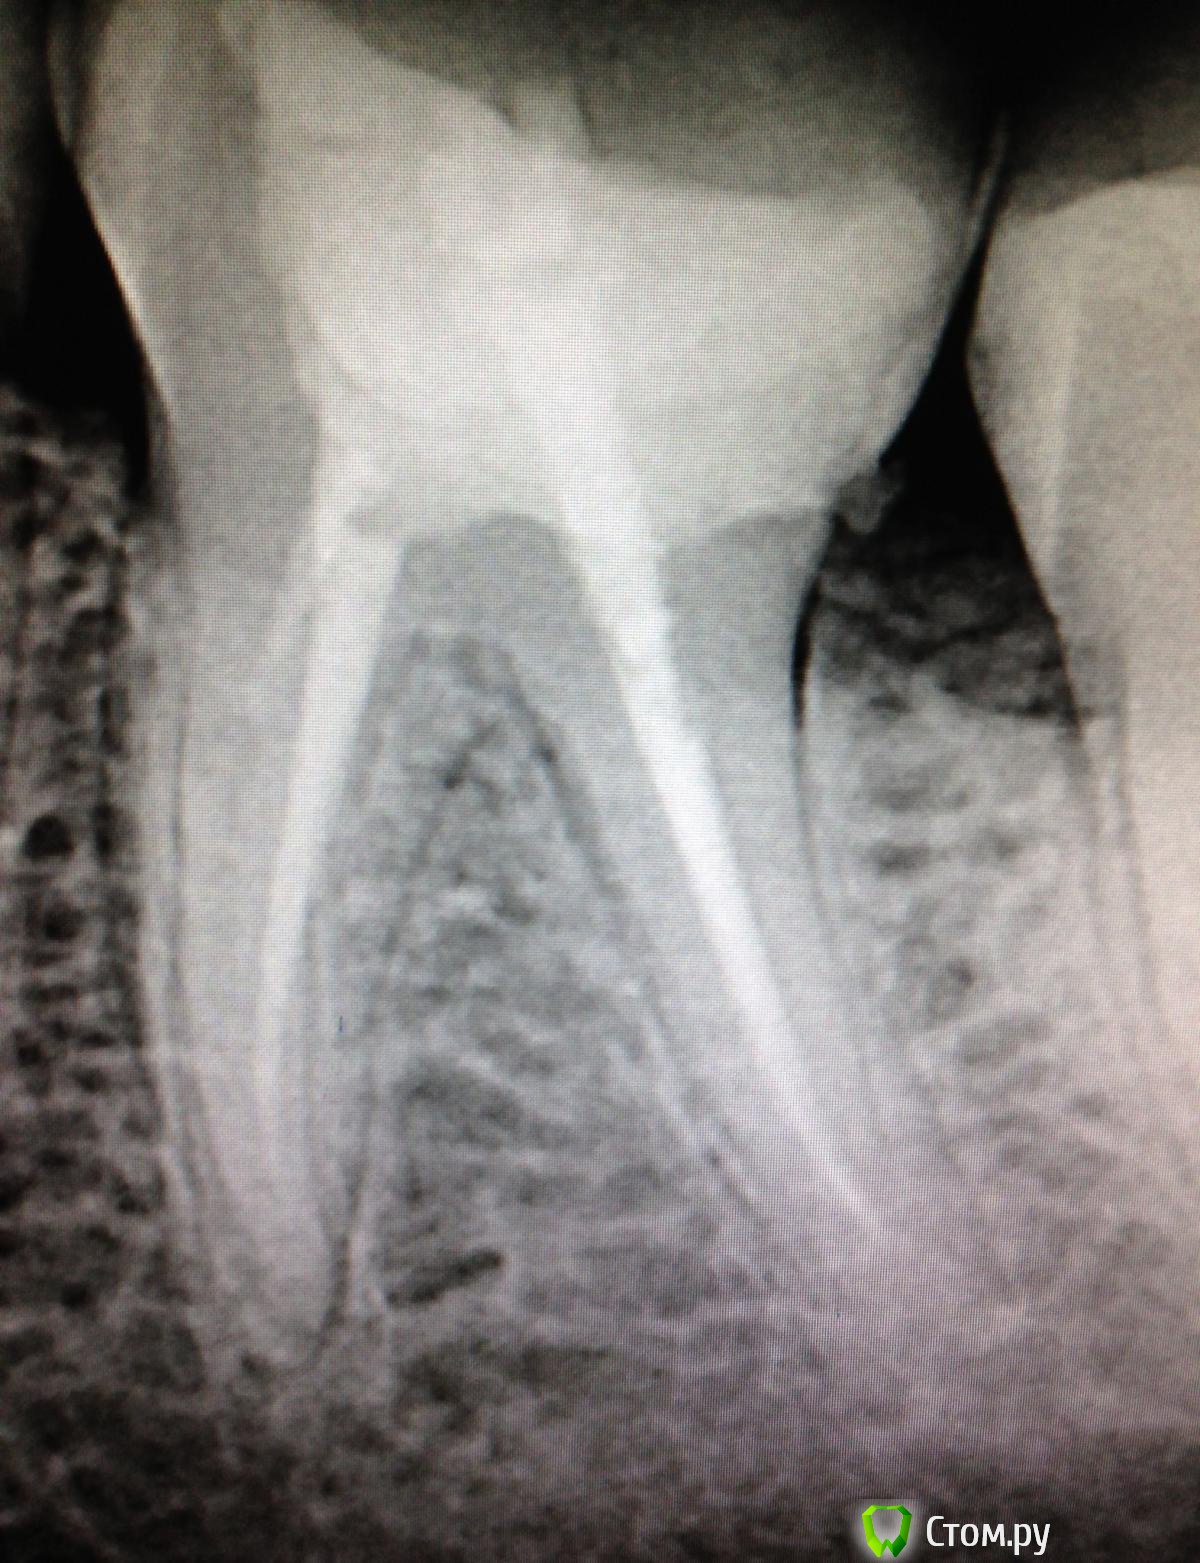

SSTi Опубликовано 2 сентября, 2014 Автор Поделиться Опубликовано 2 сентября, 2014 Кейс позора) В общем история такова. Это один из моих первых пациентов, если не первый. Только начал работать. Наконечник толком не умел держать. Ну в общем зеленый-зеленый. Диагноз не помню(пульпит или периодонтит). Это сделал я, признаюсь(года 2 назад) )))без коффера, метазоном, огромная залипуха и супер штифт на 2 мм в канале. 1 пустой. Естественно это дало обострение. Боль при накусывании и все дела. Переделал с удовольствием. Планируется вкв и мк. 3 Ссылка на комментарий